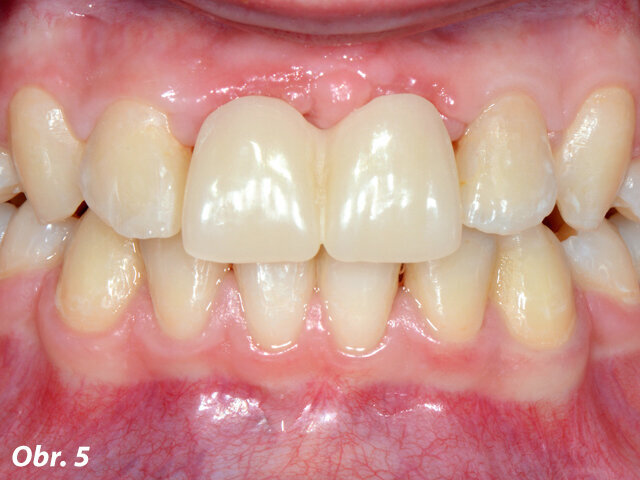

Obr. 5: Pacientka s provizorní náhradou po sejmutí ortodontického aparátu, výměně výplní a úpravě palatinální preparace zubů

Po odstranění fixního ortodontického aparátu byly původní rekonstrukce laterálních řezáků nahrazeny novými kompozitními dostavbami. Preparace na těchto zubech již byla provedena, když byl zhotovován předchozí metalokeramický můstek. Proto nebylo nutné dodatečně odstraňovat velká množství zubních struktur – palatinální preparace však vyžadovaly zahlazení. Gingiva byla ošetřena retrakční pastou. Otisk byl zhotoven pomocí skeneru 3M True Definition a odeslán do 3M frézovacího centra. Pacientka obdržela snímatelnou provizorní náhradu (obr. 5).